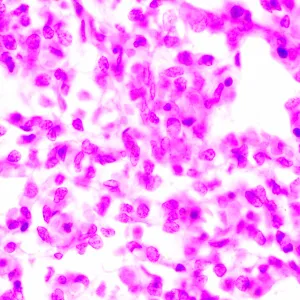

Микроскоп исследовательского класса. Предназначен для наблюдения прозрачных и полупрозрачных биологических образцов в виде мазков и срезов в проходящем свете в светлом поле. Установка опциональных компонентов позволит использовать методы темного поля, фазового контраста, люминесценции и поляризации.